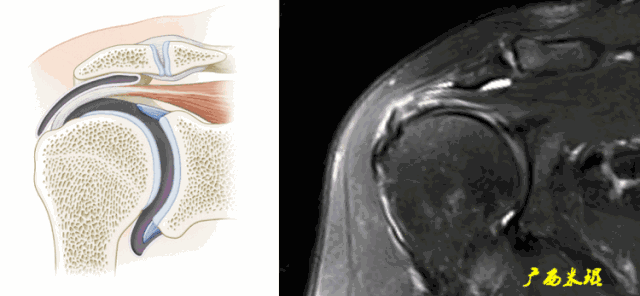

1、危险区/乏血管区信号增高

肩袖危险区在质子加权中信号增高,但是在T2W1中无信号增高,与肩袖撕裂的信号增高不同。

2、正常的腱性纤维条影

冈上肌的腱性纤维在MRI上表现为长条状低信号影,不要认为是撕裂。

3、魔角(Magic horn)效应

魔角效应在任何部位都可能发生,当肩袖的走向和磁场的方向成55度角时,局部组织的T2值会显著增加而产生类似撕裂的伪影,当TE增高或者使用STIR序列成像时魔角效应消失。

4、肱二头肌长头腱伪影

肱二头肌长头腱有时与冈上肌因间隙而出现高信号条影,或者肱二头肌长头腱本身已经有退变信号,不仔细阅片时会误认为是冈上肌撕裂信号。

5、钙化性冈上肌腱炎信号

钙化性肩袖炎主要发生在冈上肌,可以在肌腱的表面,也可以在肌腱的内部,它在MRI上表现为低信号,冈上肌腱内的不规则钙化性病灶在MR扫描中有时会不连贯,常常被误认为是肩袖撕裂。